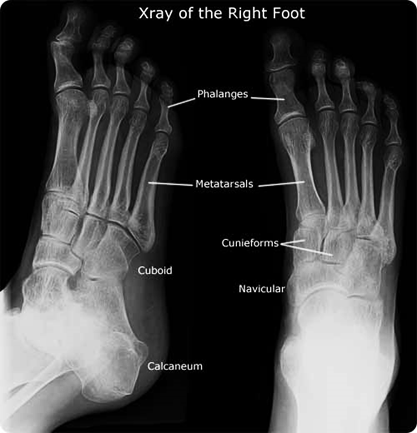

PEMERIKSAAN X-RAY KAKI - PORTAL MyHEALTH

PEMERIKSAAN X-RAY KAKI - PORTAL MyHEALTH